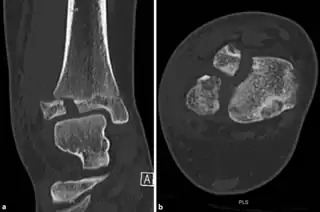

A Tillaux fracture is a Salter–Harris type III fracture through the anterolateral aspect of the distal tibial epiphysis.[1] It occurs in older adolescents between the ages of 12 and 15 when the medial epiphysis had closed but before the lateral side has done so,[2] due to an avulsion of the anterior inferior tibiofibular ligament, at the opposite end to a Wagstaffe-Le Fort avulsion fracture

The fracture commonly results from an abduction-external rotation force, causing the anterior tibiofibular ligament to avulse the anterolateral corner of the distal tibial epiphysis resulting in a Salter Harris Type III fracture.

It occurs in older children at the end of growth. Variability in fracture pattern is due to progression of physeal closure as anterolateral part of distal tibial physis is the last to close. When the lateral physis is the only portion not fused, external rotation may lead to Tillaux or Triplane fractures.[4]

• CT scan